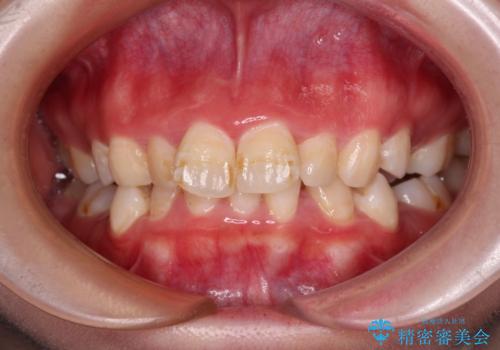

デコボコをワイヤー装置で改善 短期間で綺麗な仕上がりに

担当医 藤巻太一朗